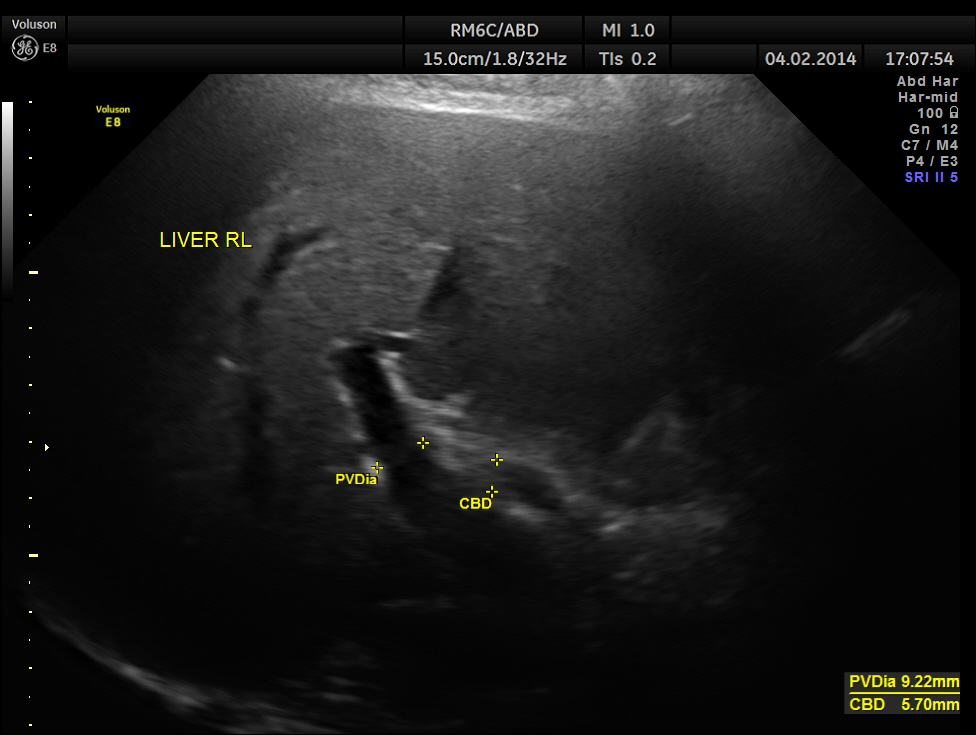

The C.B.D. measured 5.70 mms ( still within the normal range ).There was no evidence of any obstruction .

a small although statistically significant increase in the caliber of the common bile duct with increasing

age (60 years old or less, mean diameter 3.6 mm ± 0.2mm, versus over 85 years old, mean diameter 4

mm ± 0.2 mm, P = 0.009). Although the common bile duct did increase in size with aging, 98% of all

ducts remained below 6 to 7 mm, the commonly accepted upper range of normal.